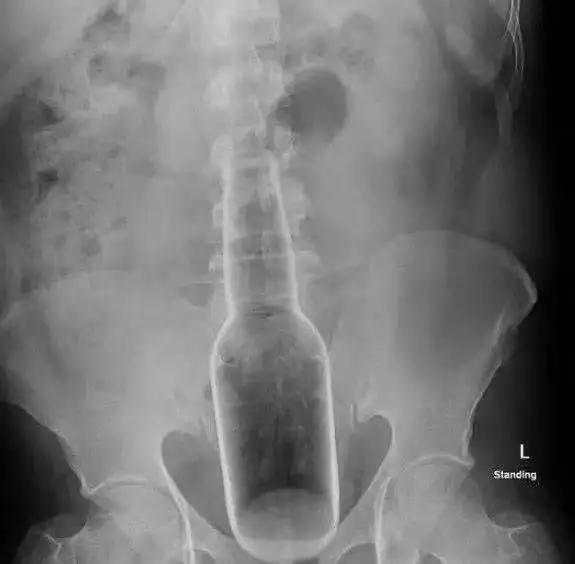

X光片显示男子的直肠里,竟有一个瓶状物!

最终医生为大叔进行了“直肠异物取出术”,这就是藏在体内的瓶子,长18cm、直径5cm的花露水瓶!